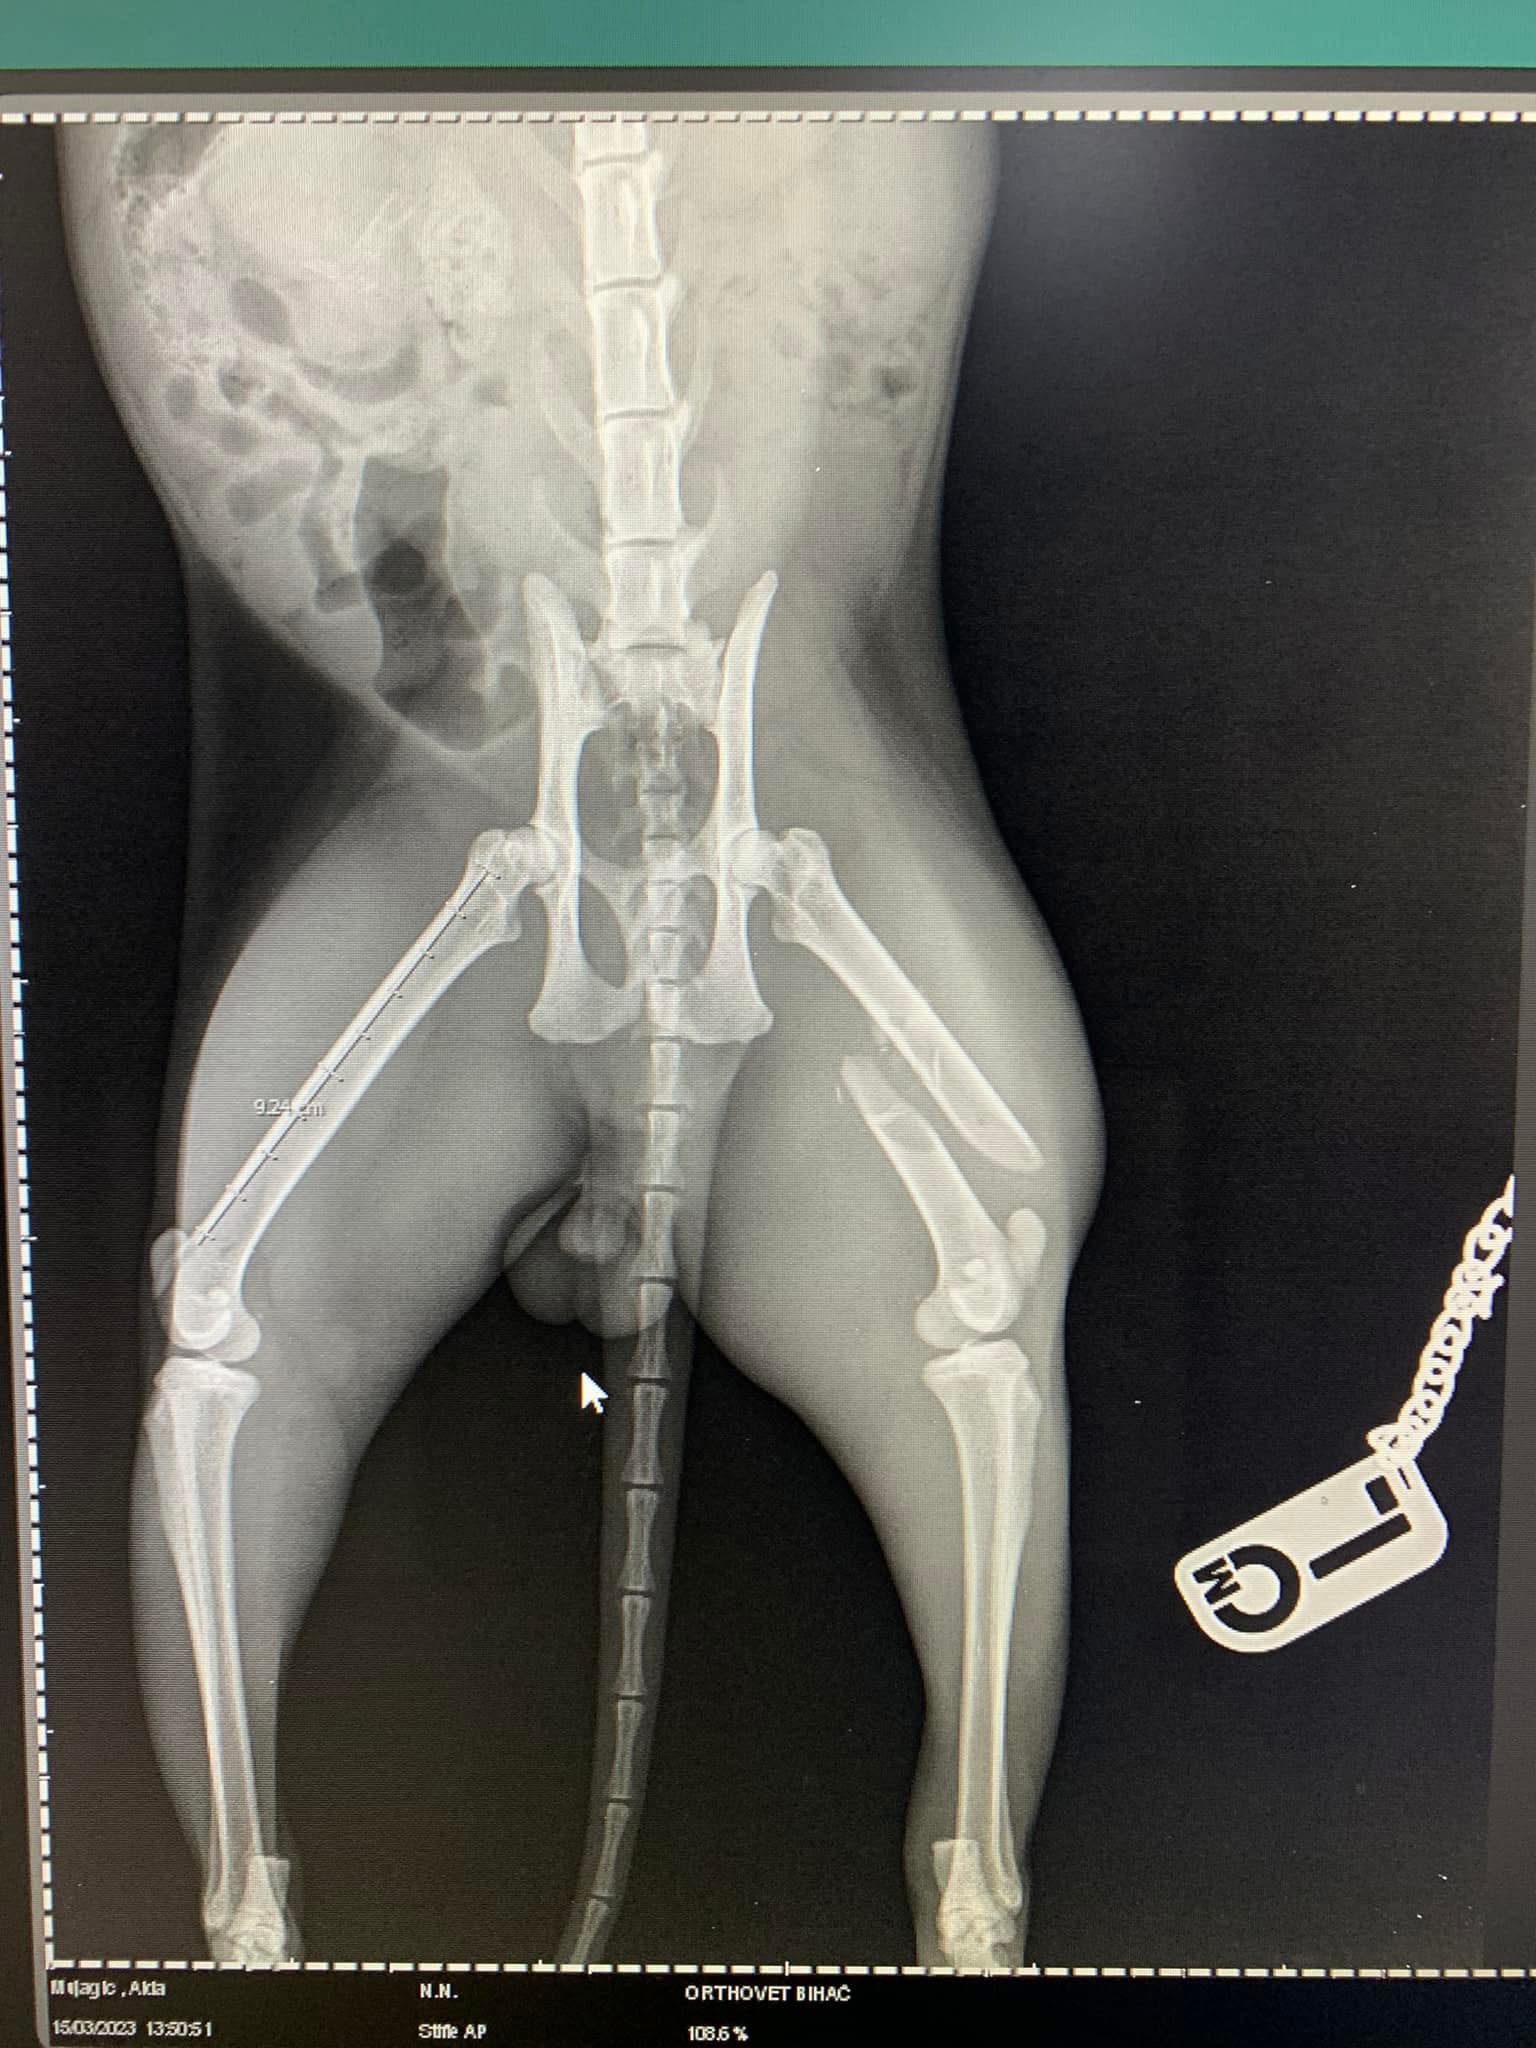

- Liječenje prijeloma kostiju, uključujući intraartikularne frakture

- Liječenje luksacije patele(Luxatio Patellae) Trohleoplastika i TTT(eng. Tibial Tuberosity Transposition)

- Liječenje rupture prednjeg križnog ligamenta koljena TPLO (eng. Tibial Plateau Leveling Osteotomy)